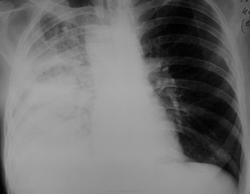

Уважаемые коллеги, хотелось бы услышать ваши мнения по поводу: 1) справа в верхней доле - полости деструкции или кисты (особенно та что выше)? 2) что могло произойти с нижней долей справа в динамике? - по ФБС только анемизация слизистых. 3) Итого, какая динамика -?

Нижнедолевая пневмония. Абсцедирование в верхней доле. В динамике - осложнение - ателектаз нижней доли.

Пневмония с абсцедированием, динамика положительная, формирование фибриноторакса. Кажется ли мне что слева за 6 ребром инфильтрация появилась ? Смотрю с нетбука (

Всем спасибо за мнения. К сожалению, это случай "архивный", дальнейшую судьбу пациентки не знаю. Я написал ателектаз нижней доли и соответственно заслал на ФБС, эндоскописты грубой патологии не увидели (в компетентности их не сомневаюсь), через день было выполнено КТ, я видел только протокол, снимки, к сожалению не могу предоставить, там оказалась справа пневмония, фиброзные изменения и полостные образования - были расценены опытным коллегой больше как кисты. Единственное что могу предположить, что эндоскописты что-то там в бронхах "расшевелили" и потом легкое, которое было в гиповентиляции расправилось. Извиняюсь, если осталась некоторая недосказанность